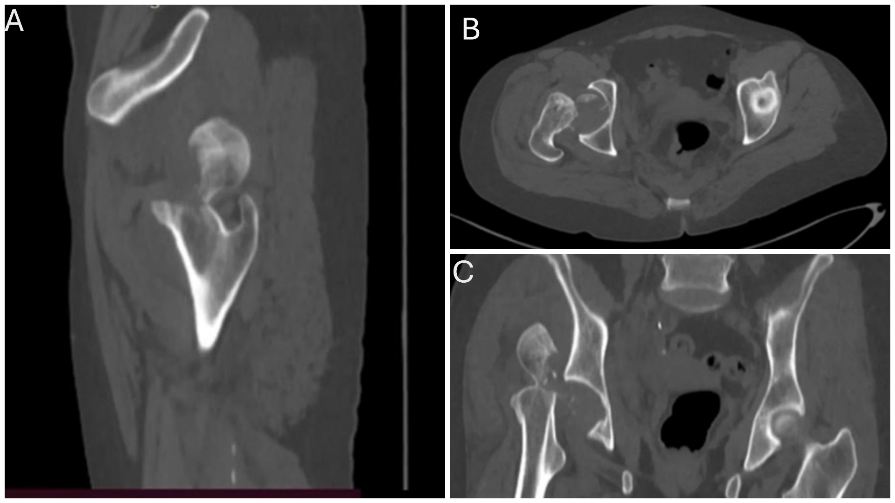

A 55-year-old female with no known comorbidities presented to the emergency department of our tertiary care center with complaints of pain in the right hip and inability to bear weight on the right lower limb following an alleged history of a road traffic accident. The patient was initially evaluated in the emergency, and her right hip was flexed, adducted, and internally rotated with no distal neurovascular deficit. There was no history of loss of consciousness, vomiting, or abdominal pain, suggesting any soft organ injury. Initial evaluations, including X-rays, revealed a posterior hip dislocation with a Pipkin type I femoral head fracture (Fig. 1). A closed reduction attempt under conscious sedation was taken, and during the reduction maneuver, while applying longitudinal traction, an audible crack was heard. Subsequently, a C-arm image was taken, and a computed tomography scan was performed, suggestive of an iatrogenic femoral neck fracture in a previously recognized femoral head fracture dislocation (Fig. 2 and 3).

Figure 3: Computed tomography of the pelvis showing femoral neck fracture in sagittal (a) and coronal view (b) showing fractured femur head fragment, (c) and axial view .